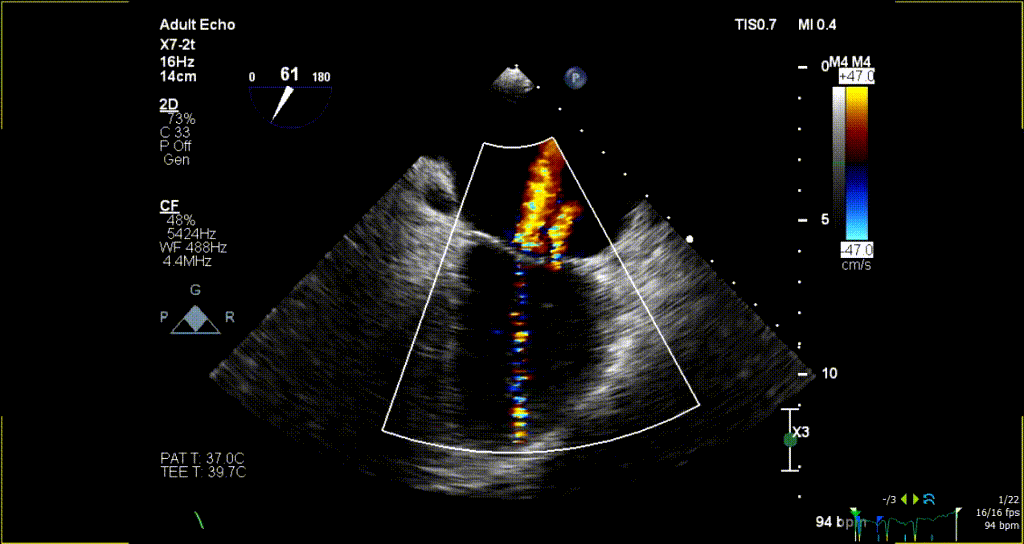

术后超声评估:

术后无反流、左室流出道通畅